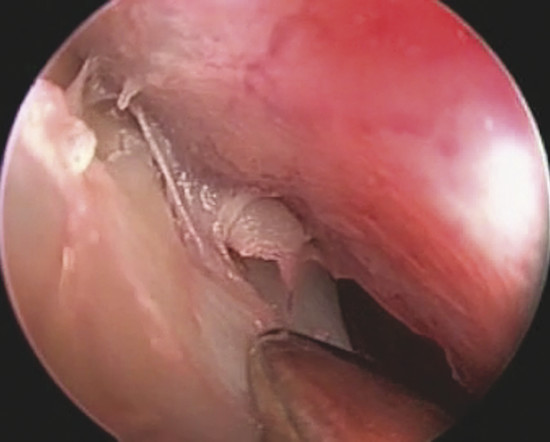

A mucoperiosteal graft is harvested from the inferior turbinate by an endoscopic turbinoplasty following Marks’ technique. 2 In particular, after injecting 2 to 3 mL of solution containing 1% Carbocaine with 1:80,000 epinephrine on inferior turbinate mucosa, over the bone, an incision on the head of the inferior turbinate with a number 15 blade along the inferior edge of the turbinate is performed. The mucoperiosteum of the nasal side of the turbinate is thus separated by a suction elevator from the underlying bone. The turbinate bone with attached lateral mucosa is then removed by endoscopic scissors till the tail of the turbinate; the residual bone can be outfractured to reduce the angle between the turbinate and lateral nasal wall. Finally the mucosa of the nasal side (previously elevated) is flipped over to cover the exposed area.

The removed part of the inferior turbinate (Fig. 19‑6) is therefore used to harvest the graft by separating the mucoperiosteum (lateral mucosa of the inferior turbinate) from the underlying bone (Fig. 19‑7). The mucoperiosteal graft is trimmed to size (minimum 1 cm of diameter larger than the perforation).